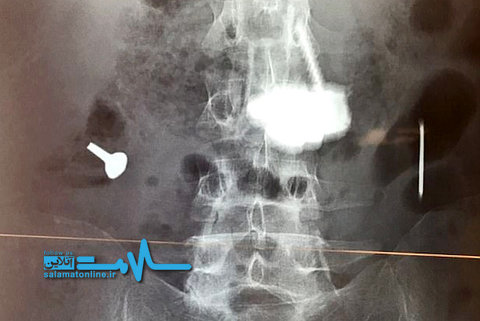

داکتران از شکم مردی ۵۲ ساله که بارها اشیاء تیز و غیرمعمول خورده بود، انبوهی از قطعات فلزی را خارج کردند.

مردی که سالها به بیماری روانی سایکوز مبتلاست و به همین دلیل عادت به بلعیدن اشیائی فلزی و غیر معمول دارد، پس از ۵ بار عمل جراحی بار دیگر در بیمارستان بستری شد و جراحان از شکمش تودهای فلز و اشیاء دیگر خارج کردند.

به نقل از بیامجیکیس ریپورت، قطعاتی که وی خورده بود در طول زمان به یکدیگر متصل شده و تودهای به نام bezoar تشکیل داده بودند که میتواند در هر جایی از دستگاه گوارش، از جمله معده شکل بگیرد.

این بیمار روانپریش که نامی از او برده نشده، طی ۵ سال گذشته و در پی درد شدید و بالاآوردن خون ناشی از تجمع قطعات مذکور، ۵ بار دیگر تحت عمل جراحی قرار گرفته بود و هر بار چیزهایی چون چاقو، ناخن، پیچ، پیچگوشتی، قاشق، ریگ و سنگریزه، سیم آهنی، و سکه از شکمش بیرون آورده شده بود.